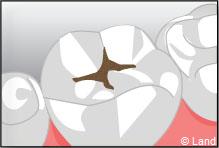

Un inlay reconstitue l’anatomie dentaire en comblant une cavité taillée dans la dent.